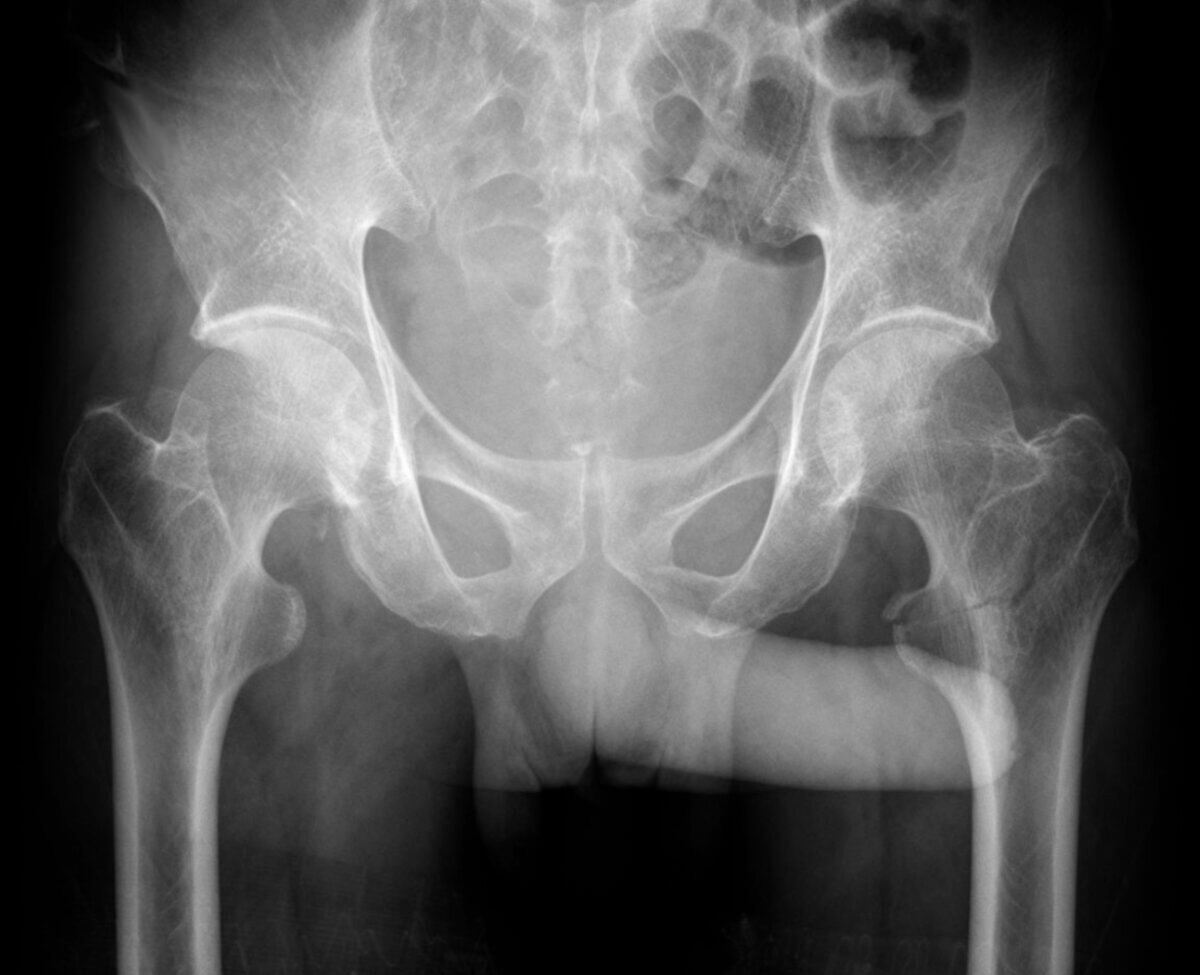

Throckmorton-Zeichen ist eine scherzhafte Bezeichnung für ein radiologisches Zeichen, bei dem der Penis auf einer Röntgen-Beckenübersichtsaufnahme in Richtung einer einseitigen pathologischen Läsion (z.B. Fraktur, Luxation) zeigt. Das Zeichen wird vor allem im Kontext von Verletzungen des Beckens oder der Hüfte erwähnt, hat aber keinen gesicherten diagnostischen Wert.